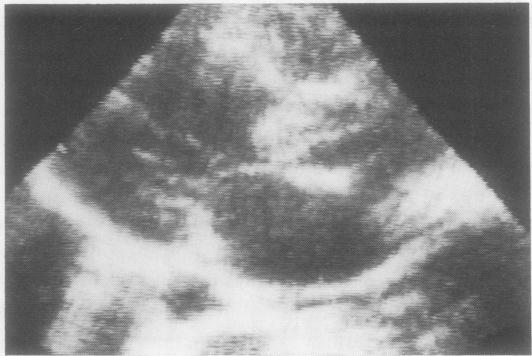

From 1972 to 1981 40 patients have required urgent valve replacement for left-sided bacterial endocarditis. The aortic valve was replaced in 31 patients, the mitral valve in four, and both in five patients. Twenty-six patients (65.5%) were in functional class IV heart failure according to the New York Heart Association criteria, and 13 patients (32.5%) were in class III heart failure at the time of operation. One patient in class II was operated on urgently for multiple cerebral embolism but died of fatal cerebral haemorrhage. In 22 patients (55%) there were no pre-existing valvular lesions and these patients were found to be more liable to develop severe haemodynamic failure. Premature closure of the mitral valve, documented by M-mode echocardiography, was a useful diagnostic aid and successfully determined the best timing of surgery in 14 out of 20 patients with severe aortic regurgitation. Cardiac arrest before operation appeared to be a significant risk factor (p = 0.0015) unless followed by immediate cardiopulmonary bypass. There were eight operative deaths (20%). Of 26 patients who were in functional class IV heart failure, 19 were operated on within four days of their haemodynamic deterioration and all survived. The operation was delayed in the remaining seven patients and none of them survived (p = 0.000003). There were no operative deaths among the patients in class III heart failure. There was only one episode of reinfection in the 16 patients followed up for at least three years. The duration of postoperative antibiotic treatment (four to six weeks in our patients), rather than any preoperative antibiotic regimen, seems to be important for preventing reinfection. At present there are 28 survivors, of whom 24 are in functional class I and four in class II.

1972年至1981年间,40例患者因左侧细菌性心内膜炎需要紧急进行瓣膜置换术。31例患者置换了主动脉瓣,4例置换了二尖瓣,5例同时置换了主动脉瓣和二尖瓣。根据纽约心脏协会标准,26例患者(65.5%)处于心功能IV级心力衰竭,13例患者(32.5%)在手术时处于心功能III级心力衰竭。1例心功能II级患者因多发性脑栓塞紧急手术,但死于致命性脑出血。22例患者(55%)术前无瓣膜病变,这些患者更容易发生严重的血流动力学衰竭。M型超声心动图记录的二尖瓣提前关闭,对诊断有帮助,在20例严重主动脉瓣反流患者中,有14例成功确定了最佳手术时机。除非紧接着进行体外循环,否则术前心脏骤停似乎是一个重要的危险因素(p = 0.0015)。有8例手术死亡(20%)。26例心功能IV级心力衰竭患者中,19例在血流动力学恶化后4天内接受手术,全部存活。其余7例患者手术延迟,无一存活(p = 0.000003)。心功能III级心力衰竭患者中无手术死亡。在至少随访三年的16例患者中,仅发生1次再次感染。术后抗生素治疗的持续时间(我们的患者为4至6周),而非任何术前抗生素方案,似乎对预防再次感染很重要。目前有28例幸存者,其中24例心功能I级,4例心功能II级。